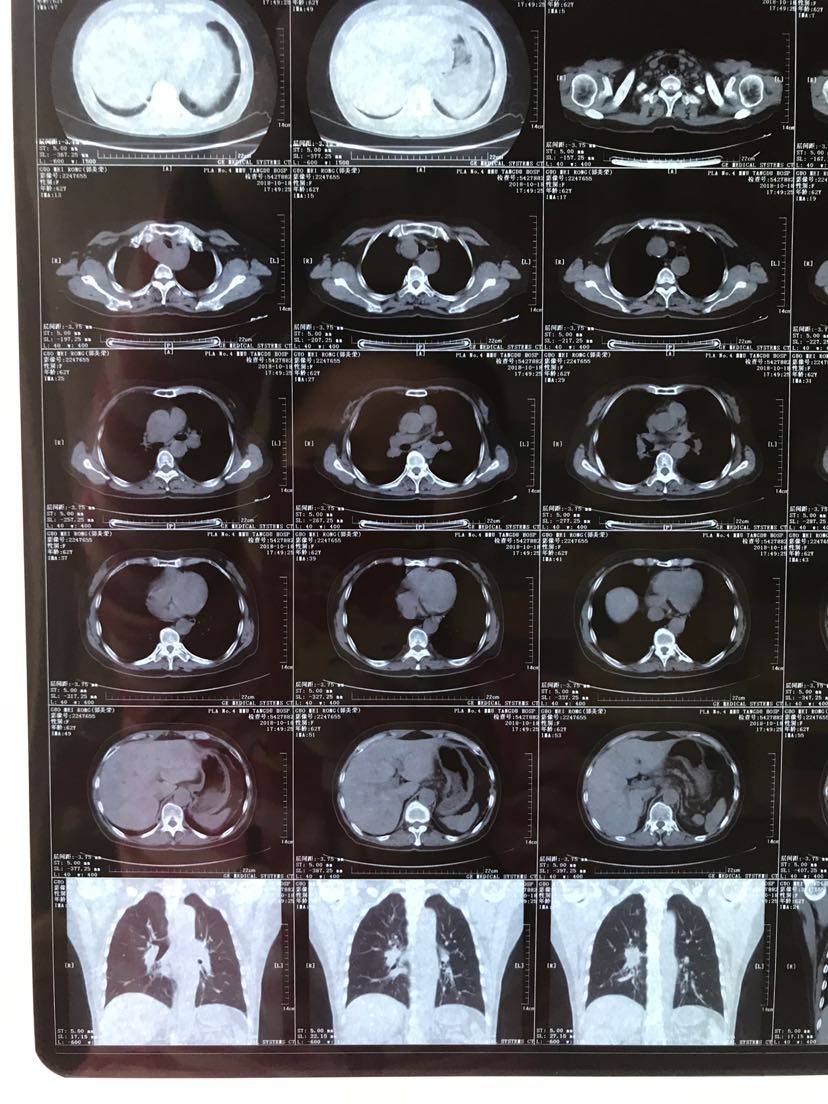

(4)

举报

然后我考虑是不是和医生商量下,趁着身体还可以,先培美加铂化疗,或者特罗凯联合贝伐?想尽量拉长一代药有效时间,同时血液基因检测,请问这么想合理吗?如果合理的话,是培美化疗还是特联贝伐的可能收益率高一点呢?

新增大的结节对特罗凯的反应应该不太敏感的,可以考虑穿插化疗看看